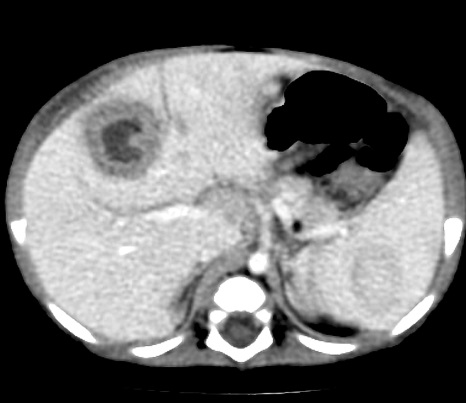

Image TDM

de abces du foie : Aspect TDM de abces du foie est

variable : lesion en apparence peripherique de hyperdensite

et a central hypodense s'observe souvent dans abces amibien . Ce qui peut en presence de

gas ( 20% de gas ) . Aspect en cloisone ou multiple

loculaire , bien definie " cluster sign" peut

se retrouve dans l'abces a pyogenes. En cas de TDM

plus de contrast intraveineuse , image de double de cible "double

target sign" peut en voyait .

Aspect radiologique TDM d'une abces

a pyogenes multi loculaire du foie en realisee sous forme de

grappe "cluster sign " . |